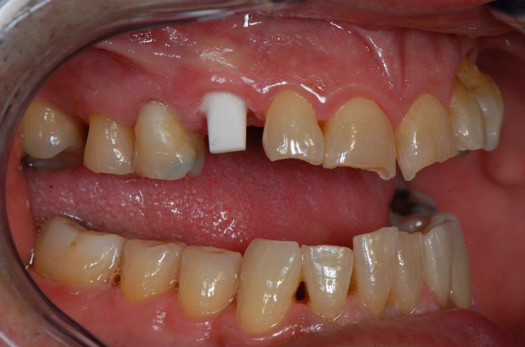

Fig 22. 12 weeks postoperatively.

Figure 22

Sutures were removed 2 weeks after surgical implant placement, and the patient was instructed to continuously wear his Essix-style retainer for 12 weeks. The retainer was worn while eating during the 12-week period. The patient returned at 12 weeks for soft-tissue and implant-bone evaluation (Figure 22). At this appointment, minimal lingual soft-tissue manipulation was performed by gingival abrasion to the keratinized soft tissue and an aluminum chloride gel was placed.